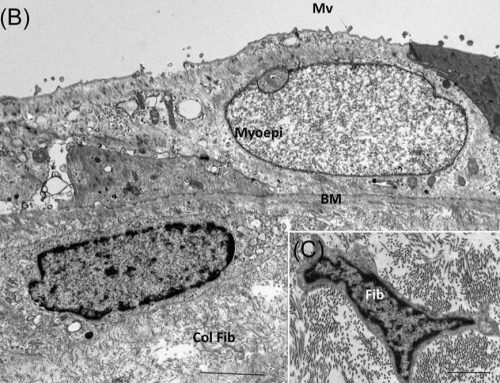

At the heart of the QEDIRA is a high-resolution 61-megapixel CMOS sensor, capable of delivering at least 15 frames per second at full resolution of 61 megapixels, ensuring crystal-clear images with fine detail. This mode is complemented by two additional 15-megapixel options. Users can select either a high-speed mode that offers an impressive 38 frames per second or a high-sensitivity mode for capturing images in low-does conditions. Whether you prioritize speed or sensitivity, the QEDIRA camera provides the flexibility to switch between modes with ease, ensuring precise results in any application.

One standout feature of the QEDIRA camera is its focus mode, which operates at full 61-megapixel resolution. With a remarkable speed of over 50 frames per second, it sets a new standard for universal TEM cameras. This feature is particularly valuable for fast, accurate focusing in a wide range of TEM workflows, reducing downtime and boosting productivity.

The QEDIRA B60T is a reflection of EMSIS’s dedication to innovation in TEM technology. With a focus on providing unparalleled image quality, resolution, and sensitivity, the QEDIRA delivers the flexibility and performance needed for a wide range of applications, from basic research to advanced industrial use.